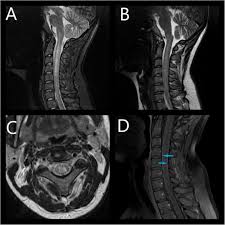

Tm is characterized by weakness and numbness of the limbs. Longitudinally extensive transverse myelitis (letm) is a specific subtype of acute transverse myelitis that usually affects three or more vertebral levels and produces m … Transverse myelitis is an inflammation of your spinal cord. Transverse myelitis is associated with viral infections, vaccinations, autoimmune processes, and cancer, although most cases are idiopathic. Our aim was to identify mr imaging findings predictive of relapse and poor outcome in patients with acute transverse myelitis of unidentified etiology. The spinal cord also carries sensory information back to the brain. Definition • transverse myelitis (tm) is a segmental spinal cord injury caused by acute inflammation 4. Myelitis, is a collective term simply referring to any inflammation of the spinal cord.

Bladder dysfunction caused by spinal cord lesions has been evaluated in multiple sclerosis, spinal cord injury, myelodysplasia, and craniovertebral junctional anomaly. Physicians also may perform myelography, which involves injecting a dye into the sac that surrounds the spinal cord. In contrast, vacuolar myelopathy is a painless spastic paraparesis which is slowly progressive and results in nonenhancing symmetric dorsolateral t2 signal. Partial transverse myelitis and partial myelitis are terms sometimes used to specify inflammation that only affects part of the width of the spinal cord. Transverse myelitis (tm) refers to a segmental inflammatory process involving the spinal cord, and may be idiopathic or secondary to a variety of specific disease processes. Able to locate the level of infection and inflammation and predict any neurological (sensory, motor) and specifically dermatomal abnormalities. When complete, both the anterior and posterior regions of the cord are involved; Spinal mris of 77 patients (mean age, 36.3 ± 20 years. Transverse myelitis is an inflammation of your spinal cord. Diffusion tensor imaging in idiopathic acute transverse myelitis. Lee jw (1), park ks, kim jh, choi jy, hong sh, park sh, kang hs. Lumbar puncture (spinal tap) uses a needle to draw a small amount of cerebrospinal fluid (csf), the protective fluid that. Idiopathic transverse myelitis is a

Transverse myelitis is an inflammation of the spinal cord, the part of the central nervous system that sends impulses from the brain to nerves in the body. Acute transverse myelitis is an inflammatory disorder of the spinal cord in which there is no evidence of spinal cord compression. An mri can show inflammation of the spinal cord and other potential causes of the symptoms, including abnormalities affecting the spinal cord or blood vessels.; Magnetic resonance imaging (mri) uses a magnetic field and radio waves to create 3d images of soft tissues. Hiv myelitis often occurs in association with hiv encephalitis and reflects direct viral infection of the cord with a similar clinical and imaging appearance to transverse myelitis 57. This neurological disorder often damages the insulating material covering nerve cell fibers (myelin). It typically presents with acute or subacute flaccid paraparesis, sensory abnormalities, and bowel/bladder dysfunction. The two major sub types include: Acute complete tm refers to complete or near complete clinical deficits below the lesion and an mri lesion of less than 3 vertebral segments. A case of transverse myelitis following catheterization of the right fifth intercostal artery is reported here to emphasize the fact that bronchial arteriography does carry some hazard which must be assessed in the light of the presenting clinical problem. Atm comprises a subgroup of the noncompressive transverse myelopathies. Further criteria divide transverse myelitis into two main groups. Transverse myelitis (tm) refers to a segmental inflammatory process involving the spinal cord, and may be idiopathic or secondary to a variety of specific disease processes.